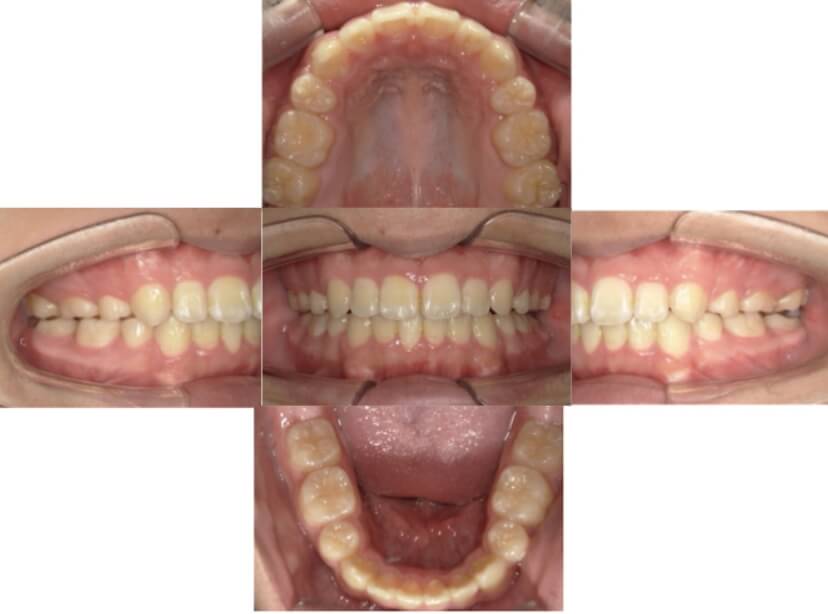

BEFORE

AFTER

上下顎叢生、上顎前突(出っ歯、上下の前歯のガタガタ)のケースです。

装置はラビアル(上下表側)で、上顎の小臼歯を2本抜歯を行っています。抜歯したスペースを使って、上の前歯の後方移動と叢生(ガタガタ)と出っ歯の改善を行っています。下は歯と歯の間にIPR(隣接面削合)を行い、スペースを確保し、叢生の改善を行っています。

主訴 前歯のガタガタと出っ歯が気になる。

年齢・性別 47歳 女性

治療方針 抜歯スペースおよびIPRを利用して上前歯の叢生(ガタガタ)の改善

抜歯部位 上顎左右第一小臼歯

使用装置 ラビアル(上下表側)、顎間ゴム

治療期間 2年0か月

治療回数 15回

リテーナー クリアリテーナー